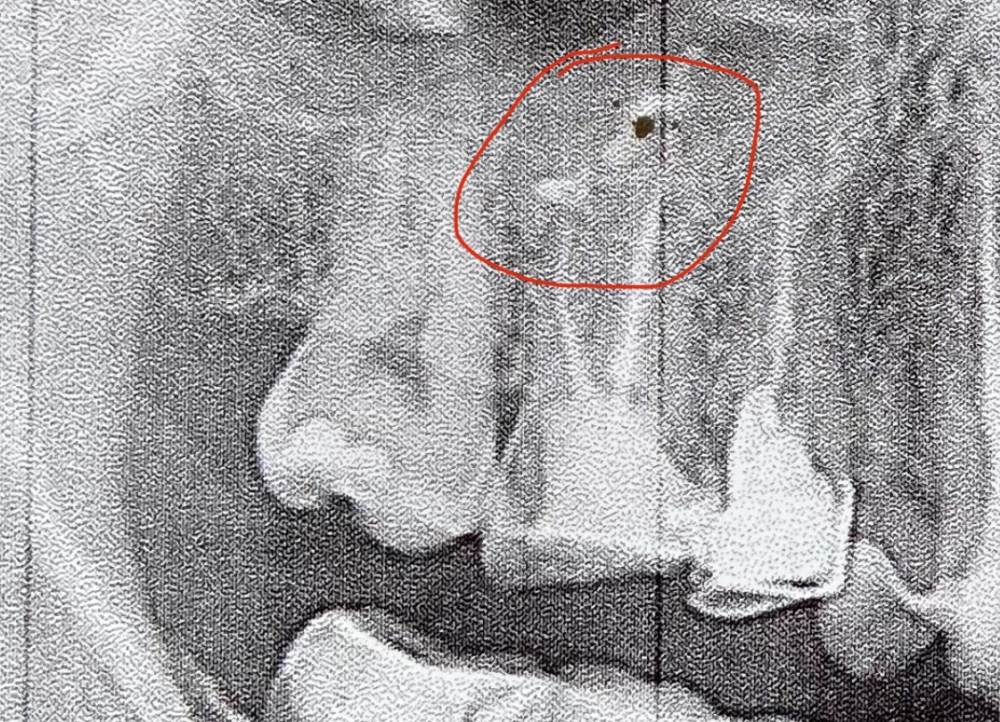

Галечная Опубликовано 24 октября, 2021 Поделиться Опубликовано 24 октября, 2021 (изменено) Здравствуйте! Два года назад пролечили пульпит. Сейчас зуб начал болеть при надкусывании. Терпела 2 недели, думала пройдёт само, ведь бывало такое на пару дней. Не выдержала, пришла к своему новому доктору. Она предположила, что пропущен канал. Когда рассверливала пломбу, запах был неприятный. Канал нашла. Обработала и заложила лекарство. Дальше временная пломба на месяц. Было все терпимо, но к вечеру второго дня (сегодня) зуб начал ныть сильнее, на десне отёк. Врач сказал, что может болеть. Но, если боль нарастает, придти, открывать канал. Вот думаю, как отличить боль от патологической. на фото этот зуб перед приемом. Что там такое наверху? Пломбировочный материал? П.с прочла про передонтит (это ведь он у меня), жутко расстроилась Изменено 24 октября, 2021 пользователем Галечная Ссылка на комментарий

red_butler Опубликовано 25 октября, 2021 Поделиться Опубликовано 25 октября, 2021 Здравствуйте, снимок не информативен 1 Ссылка на комментарий